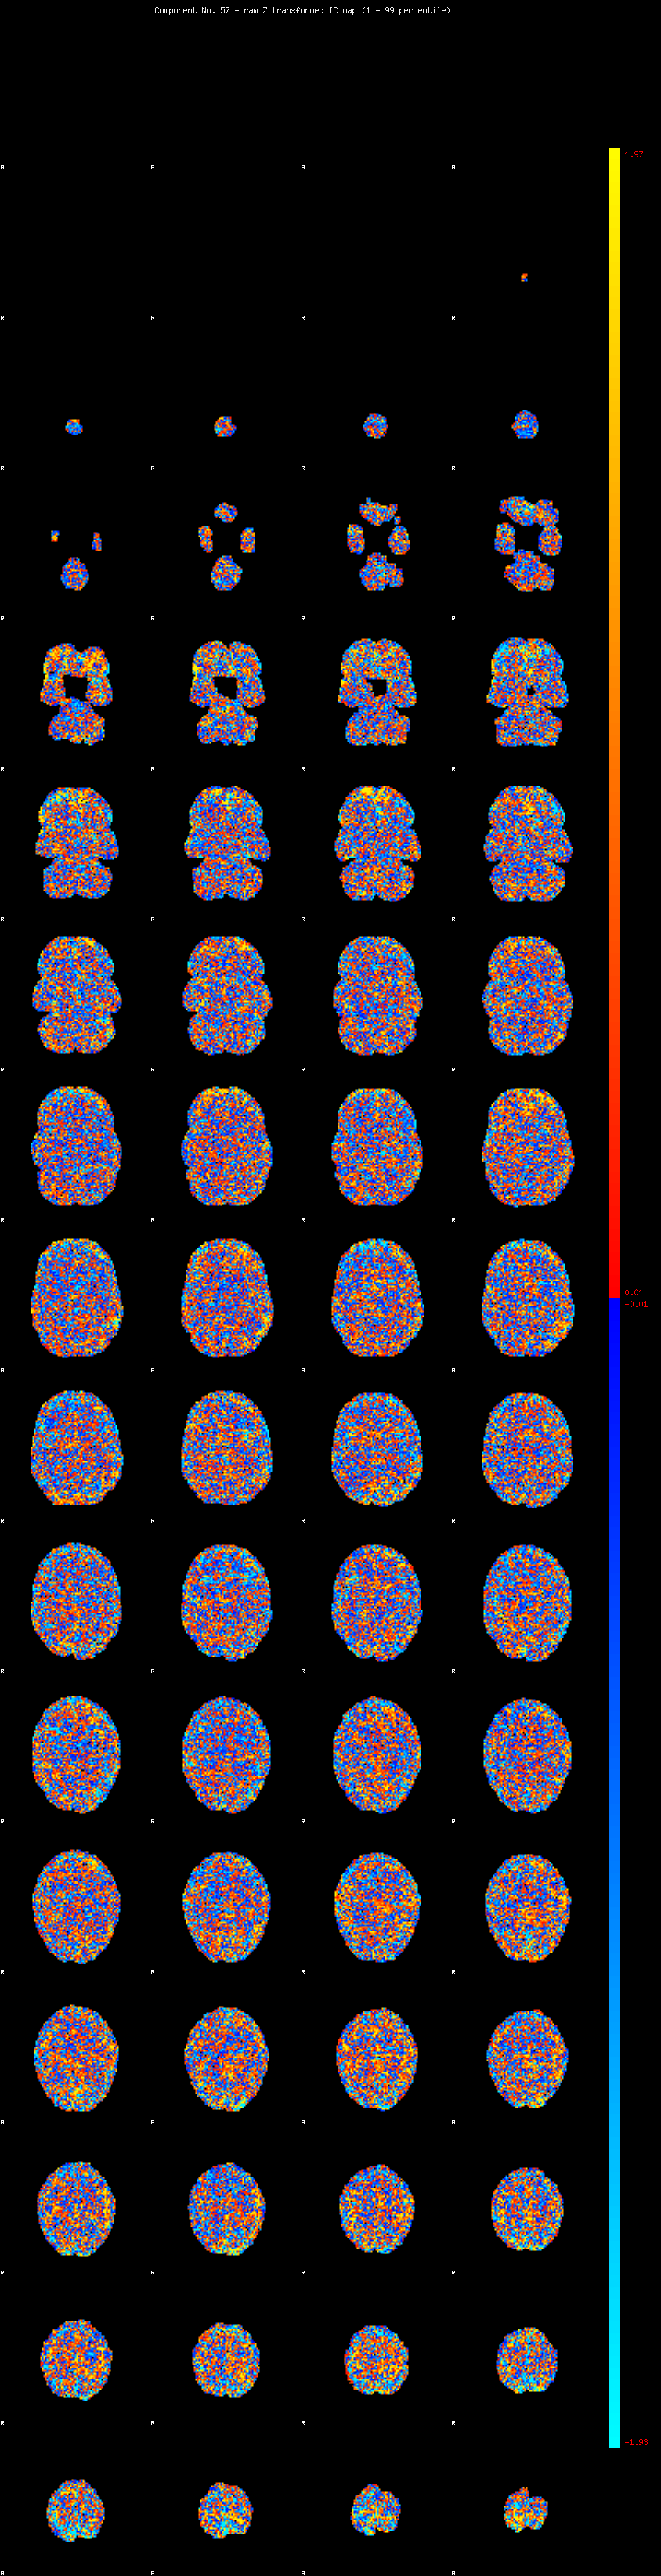

IC_57 Mixture Model fit

Means : -0.000000 2.238712 -2.177601

Vars : 1.000000 1.282181 1.123885

Prop. : 0.936753 0.033046 0.030200